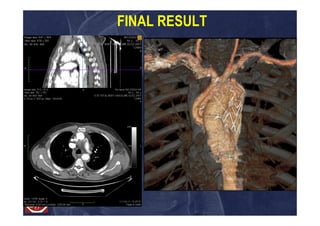

FINAL RESULT

Multibranched Frozen ElephantTrunk Clinical Case 1 59 yo man Acute aortic Type A dissection: arch entering tear Not complicated (Penn Class Aa) Surgical treatment: Multibranched – FET with Captivia- Medtronic-VAMC 32-32-150